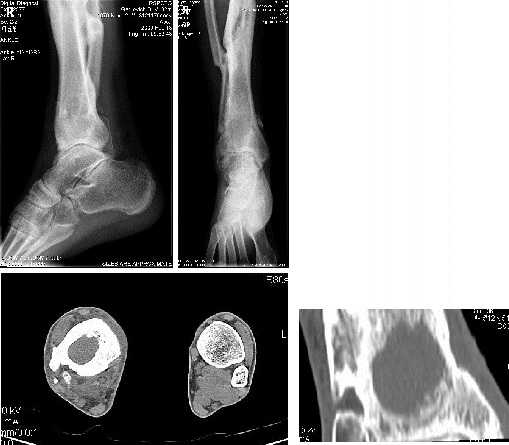

У пациента 31 года после ВКДО голени по Илизарову хронический остеомиелит дистального отела большеберцовой кости.

Пацент лечится у нас с 2005 года когда по поводу несращения с/3 голени был применен ВКДО по Илизарову. Достигнута консолидация, аппарат демонтирован. Через 2 года после снятия аппарата появился свищ над внутренней лодыжкой. Осенью 2007 года - ФНЭ, аутопластика дефекта метафиза аутоспонгиозой из проксимального отдела большеберцовой кости - в течение года ремиссия.В ноябре-декабре 2008 вновь открылся свищ, произведена хирургическая обработка, в настоящее время скудное серозное отделяемое. Конечность полностью опорна, болей нет.Вопрос: чем лучше заполнить дефект метафиза: губкой из крыла подвздошной кости или каким-либо заменителем (хотя инфицирование остается)?Спасибо,Александр Ситник

Средняя треть большеберцовой кости еще благоприятное для лечения место. Для оценки протяженности процесса целесообразна спиральная томография голени. Обязательна некроэктомия, лаваж раны с использованием нетоксичных антисептиков и ПАВ, тугое заполнение полости аутокостью. Ньюанс состоит в том, что чем больше будет нарушено кровоснабжение в оперируемой зоне, тем меньше вероятность положительного исхода, поэтому важно предоперационное планирование. В послеоперационном периоде обязательно внутрикостное введение антибиотиков до заживления раны (сейчас рекламируют гентамициновые гранулы).